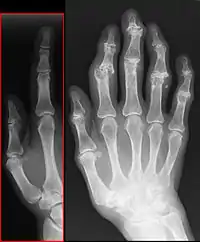

La radiographie standard, sans préparation, est suffisante au diagnostic de la maladie arthrosique.

Quatre signes radiologiques sont caractéristiques :

- le pincement de l'articulation par destruction du cartilage (diminution de l'épaisseur du cartilage) ;

- une condensation osseuse sous le cartilage ;

- la présence d'excroissances osseuses ou ostéophytes ;

- la présence de géodes (trous à l'emporte-pièce) dans l'os autour de l'articulation.

Il n'y a pas de parallélisme entre l'importance des signes radiographiques et les symptômes ressentis : une arthrose importante sur la radiographie peut rester asymptomatique. Inversement, une arthrose très douloureuse peut ne présenter que de modestes altérations radiologiques.